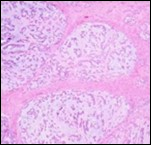

Figure 1.Parachordoma on fine needle aspiration cytology depicting clusters of spheroidal cells with eosinophilic cytoplasm, regular nuclei and clumped, encompassing myxoid stroma 13.

Figure 2.Parachordoma delineating clusters of vacuolated, spherical cells with acidophilic cytoplasm, uniform nuclei and an immune non reactive CD34- 13.